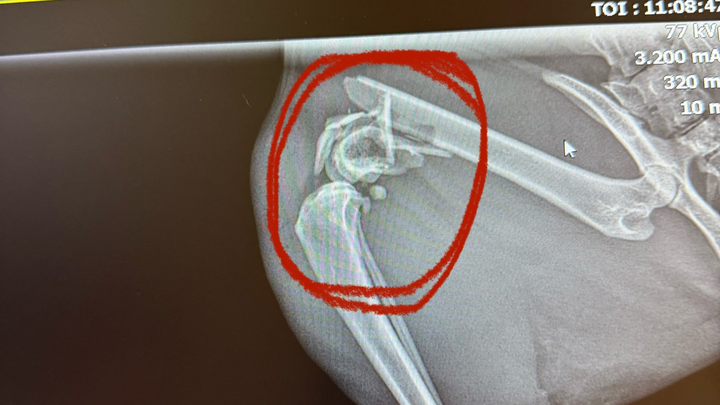

Hello everyone, I am needing YOUR help!!! This is our sweet boy Calcifer! Unfortunately, he will have to get his leg amputated due to his leg fracture. He has a comminuted fracture which is a more serious leg fracture that doesn’t just break clean, his bone broke into multiple pieces and if we were to get his surgery for his leg then it would be anywhere from $6k-$8k which we know we won’t be able to fund in time if he were to have the surgery. We have applied for Care Credit and hoping they accept us. It would really help us out in the long run if they were to accept us but for now we are trying our hardest to raise the funds for his amputation. They also told us If he were to have the surgery then there would be a 20% rate that he wouldn’t make it through and we rather not risk that 20% and they said if he were to have it then it could also still give him problems in the future, so amputation is our best option. His amputation treatment is $1,454 and so far the gofundme is really pushing it and i’m so very grateful for every dollar that has been sent for my sweet boy. We would like to get his amputation done next thursday! I genuinely am desperate and asking for anything anyone can give so my sweet boy doesn’t have to be in pain anymore. Please share with family members and on your social medias!! post the link as much as you can so this can reach where it needs to be!! anything genuinely helps!!